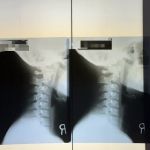

- Pain Management for Various Conditions: The practice provides targeted relief for a wide range of conditions, including but not limited to, back pain, neck pain, hip pain, headaches, sciatica, and joint stiffness. The goal is to identify the source of discomfort and develop a treatment plan to address it.